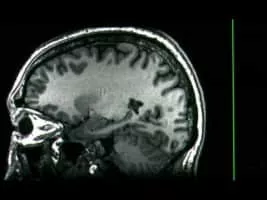

Dr. Richard Davidson, a brain specialist, experiments with meditation and yoga as a means of helping soldiers with PTSD and children with ADHD.